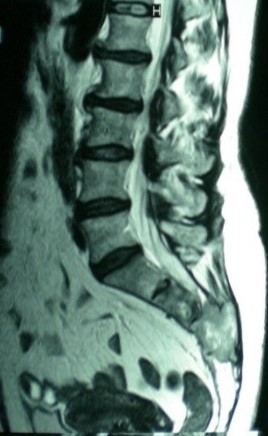

Partial sacrectomy by single posterior approach.